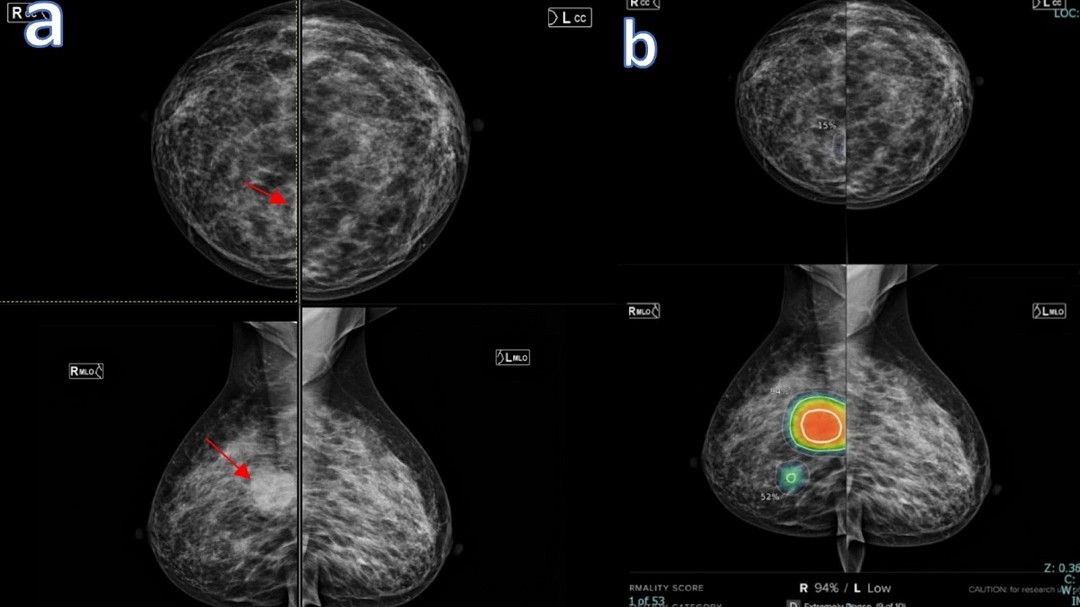

วารสารทางการแพทย์ระดับโลกอย่าง The Lancet Digital Health รายงานว่า ทีมวิจัยจากออสเตรเลีย นำโดย St Vincent’s BreastScreen Melbourne ได้พัฒนาอัลกอริทึมครื่องมือ AI ตัวใหม่ที่ชื่อว่า BRAIx ที่ไม่ได้ทำหน้าที่เพียงแค่หาจุดมะเร็งในปัจจุบัน แต่ทำหน้าที่พยากรณ์โอกาสเกิดมะเร็งในอนาคต โดยใช้ข้อมูลจากภาพเอกซเรย์เต้านม (Mammograms) ของผู้หญิงเกือบ 400,000 คน

งานวิจัยพบว่า ผู้หญิงที่ AI จัดให้อยู่ในกลุ่มเสี่ยงสูงสุด 2% แรก มีโอกาสเกิดมะเร็งเต้านมภายใน 4 ปีอยู่ที่ 9.7% หรือเกือบ 1 ใน 10 คน ซึ่งเป็นระดับความเสี่ยงที่สูงเท่ากับหรือมากกว่าผู้ที่มีการกลายพันธุ์ของยีน BRCA1/2 ซึ่งเป็นยีนก่อมะเร็งเต้านมที่อันตรายที่สุด AI ยังสามารถตรวจพบรูปแบบความผิดปกติที่ซับซ้อนในเนื้อเยื่อ ซึ่งรังสีแพทย์อาจมองว่าเป็นเนื้อเยื่อปกติหรือเป็นเพียงความหนาแน่นของเต้านมทั่วไป